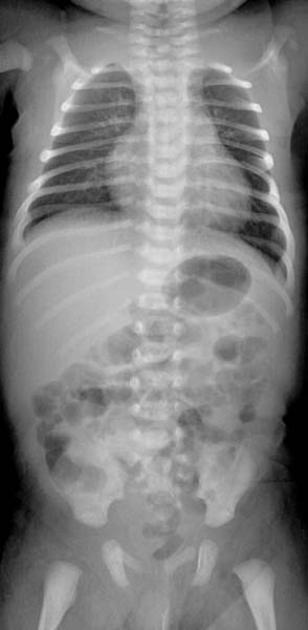

2.5 year old boy who won’t bear weight

Osteomyelitis

typical appearance and location for osteomyelitis.

Extension into the epiphysis is typical; may be seen with tumors but more common with osteomyelitis.

The diffuse sclerosis surrounding the lytic lesions represents typical host reaction to the infection.